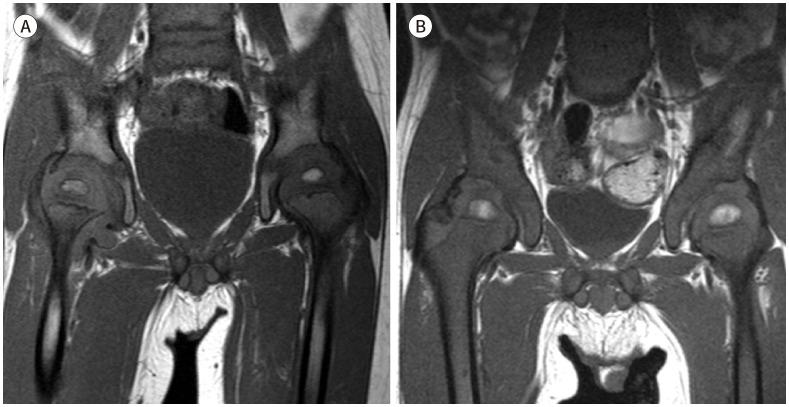

MRI plays a crucial role in bone marrow (BM) assessment, and has very high sensitivity in diagnosing marrow disorders. However, for radiologists who may not frequently encounter pediatric imaging, distinguishing pathologic BM lesion from normal BM can be challenging. Conditions involving the BM in pediatric patients, such as leukemia and metastatic neuroblastoma, often manifest with diverse musculoskeletal symptoms and may be diagnosed using musculoskeletal MRI examinations. Accurate interpretation of pediatric MRI requires not only an understanding of the normal composition of BM but also an awareness of agerelated developmental changes in the marrow and familiarity with conditions that commonly involve pediatric BM. We aim to describe the composition of normal BM and outline the normal and abnormal MRI findings in pediatric BM. Additionally, we aim to present clinical cases of malignant BM disorders including leukemia, neuroblastoma metastasis, and other malignant BM disorders.

磁共振成像(MRI)在骨髓(BM)评估中起着至关重要的作用,并且在诊断骨髓疾病方面具有很高的敏感性。然而,对于可能不经常接触儿科影像的放射科医生来说,区分病理性骨髓病变与正常骨髓可能具有挑战性。儿科患者中涉及骨髓的疾病,如白血病和转移性神经母细胞瘤,通常表现为多样的肌肉骨骼症状,可通过肌肉骨骼MRI检查进行诊断。准确解读儿科MRI不仅需要了解骨髓的正常组成,还需要认识到骨髓中与年龄相关的发育变化,并熟悉常见累及儿科骨髓的疾病。我们旨在描述正常骨髓的组成,并概述儿科骨髓的正常和异常MRI表现。此外,我们旨在展示包括白血病、神经母细胞瘤转移和其他恶性骨髓疾病在内的恶性骨髓疾病的临床病例。